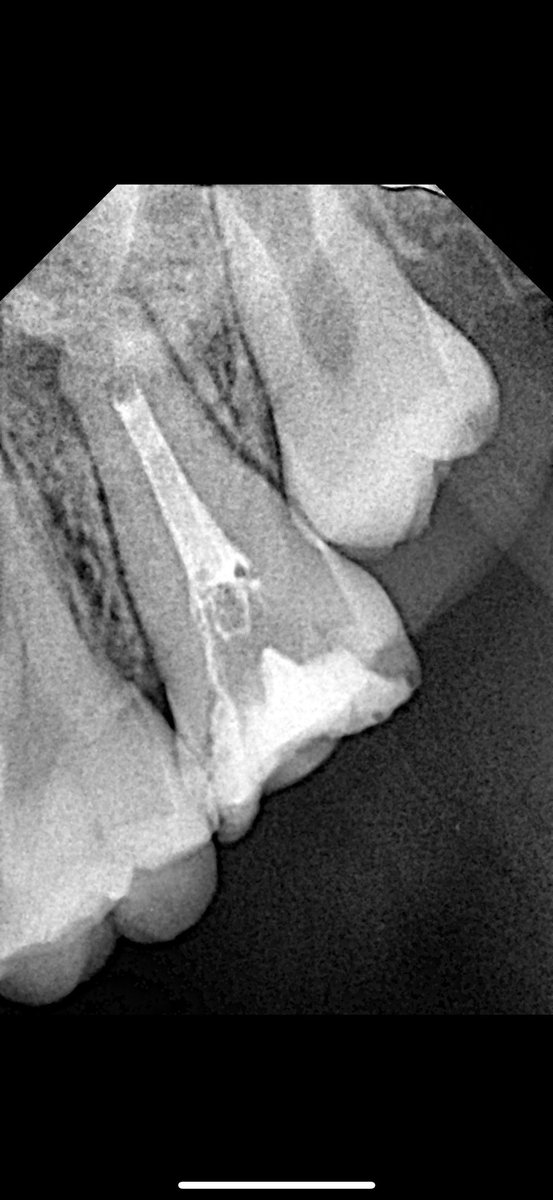

@Dr_abubakr1 @Mohammed1soo @HrbiHaneen @mutaz_alj @Khalid_6dent @amallllll775 الله يسلمك دكتورنا 🙏 ، تعتمد على الحاله بس هنا استخدمت راوند بير وحبيت تكون minimal عشان عليها كران